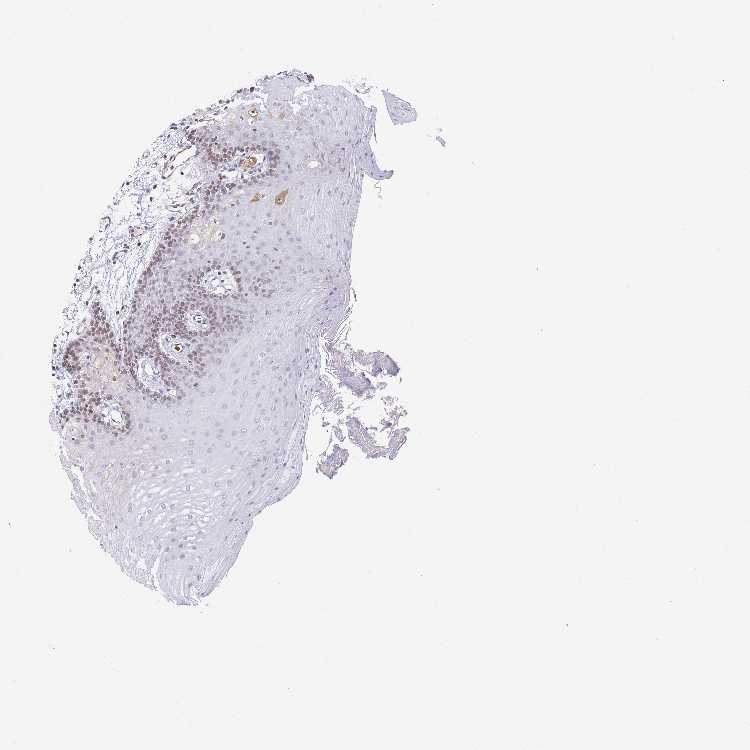

TISSUE PRIMARY DATA ORAL MUCOSA Show tissue menu

ORAL MUCOSA - Antibody stainingi

Antibody staining in the annotated cell types in the current human tissue is reported as not detected, low, medium, or high, based on conventional immunohistochemistry profiling in selected tissues. This score is based on the combination of the staining intensity and fraction of stained cells.

Each image is clickable and will lead to virtual microscopy that enables deeper exploration of all samples and also displays staining intensity scores, fraction scores and subcellular localization as well as patient and tissue information for each sample.

Antibody HPA002196Antibody CAB020668

Squamous epithelial cells LowNot detected